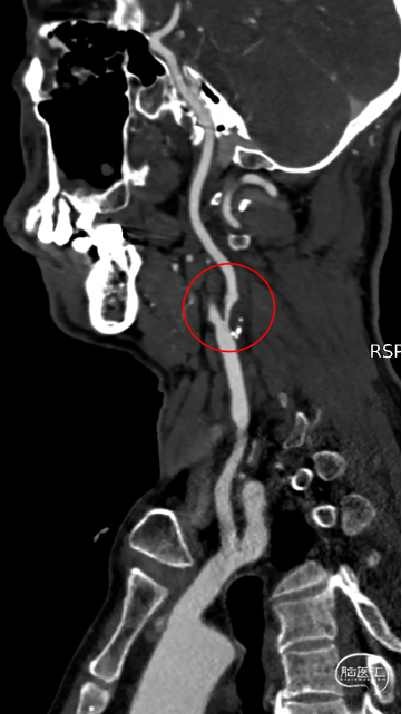

CTA提示:右侧颈内动脉起始部重度狭窄。

以260cm泥鳅导丝辅助125cm Simmons 2和6F导引导管超选右侧颈总动脉远端,撤出泥鳅导丝及造影管,再次造影可见右侧颈内动脉起始部重度狭窄,狭窄率约80%。